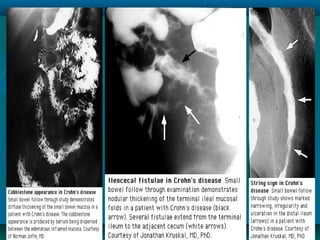

Cobblestone appearance is characteristic of CD (both

endoscopically and by barium radiography)

Cont…



Active CD is characterized by focal

inflammation and formation of fistula tracts

The bowel wall thickens and becomes

narrowed and fibrotic, leading to chronic,

recurrent bowel obstruction

serpiginous ulcer, a classic finding in Crohn's disease